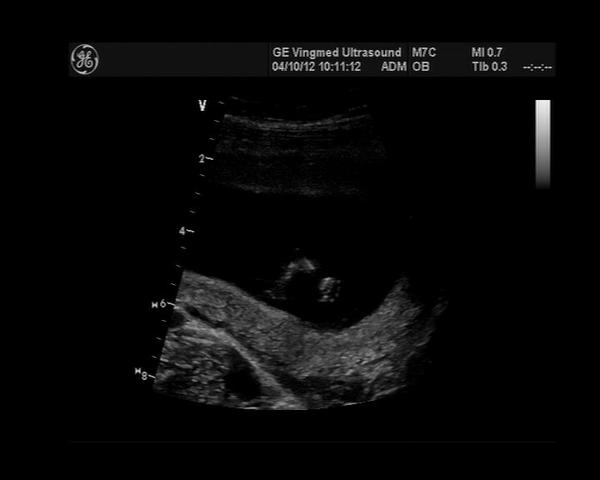

@briuska Ahoj Lucko, tak včera u pana primáře kontrola UZ, plodové vejce má 13,4mm což dle doktora odpovídá 5+1, ale včera jsem měla být 6+3. Jo a má srdíčko 🙂. Tak nevím jak to počítají, další KO až 14.10. Ještě ležím, dnes tedy už tak z poloviny, to flákání mě už nebaví. Ale snažím se šetřit jak nařídili klidový režim.

@elliem Ahoj, no právě že primář řekl, že je menší, ve zprávě mám napsáno: plodové vejce o průměru 13,4mm. Jsem z toho jelen. Už jsem se dost o asistované reprodukci poučila, ale MUDr. nejsem. Počítám to od po¨slední menstruace. Ale říkal že je to ok. No koukala jsem i na tabulky, ale podle toho to nějak nevyčtu. Musím prostě počkat...